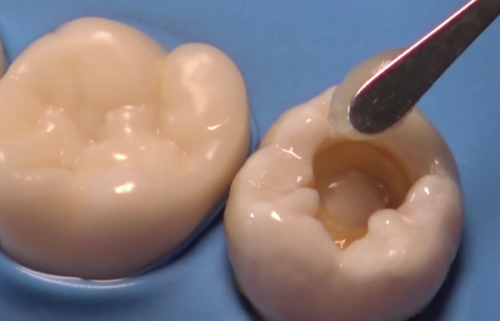

文章围绕补牙材料展开,指出没有绝对“最好”的材料,需综合考量。介绍了复合树脂、玻璃离子水门汀等多种材料,各有优缺点,如复合树脂美观实用但有微渗漏风险,银汞合金耐磨价廉却不美观。还给出选择建议,前牙重美观,后牙重强度,特殊人群选生物相容性高的材料。强调补完牙要做好日常维护,综合多因素选适合自己的材料。

本文围绕补牙齿的填充物维持时间展开。其维持时间因材料和口腔状况而异,一般数年至数十年不等。银汞合金可维持 5 - 10 年甚至更久,复合树脂和玻璃离子水门汀常用且持久。影响因素有填充物类型、材料质量、医生技术和口腔卫生等。出现特殊情况要及时处理,还可通过保持清洁、避免咬硬物、定期检查来延长其寿命。

本文围绕“补牙怎么补”介绍了3个关键步骤。补牙前,清理龋坏组织,不同程度龋坏处理方式有别,怕疼可局部麻醉。补牙时,根据牙齿缺损情况选择直接填充、嵌体修复、全冠修复或根管治疗。补牙后,2小时内避免进食,24小时不用患侧嚼硬物,养成良好口腔卫生习惯,定期检查,控制甜食摄入。